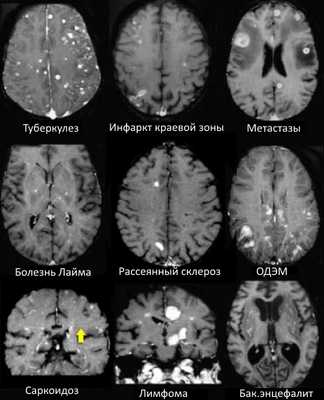

На изображениях определяются множественные точечные и «пятнистые» очаги (некоторые из них будут рассмотрены более детально).

Рассеянный склероз — хроническое аутоиммунное заболевание, при котором поражается миелиновая оболочка нервных волокон головного и спинного мозга, характеризующееся многоочаговостью поражения белого вещества центральной нервной системы, ремиттирующе-прогредиентным течением, вариабельностью неврологических симптомов и преимущественным поражением лиц молодого возраста (подробнее с диагностическими критериями указанного заболевания Вы можете ознакомится в статье «Современные критерии диагностики рассеянного склероза», опубликованной на нашем сайте).

Саркоидоз головного мозга

- Распределение очаговых изменений при саркоидозе крайне напоминает таковое при рассеянном склерозе.

Прогрессирующая мультфокальная лейкоэнцефалопатия (ПМЛ)

- Демиелинизирующее заболевание, обусловленное вирусом Джона Каннигема у пациентов с иммунодефицитом. Ключевым признаком являются поражения белого вещества в области дугообразных волокон, не усиливающиеся при контрастировании, оказывающие объемное воздействие (в отличие от поражений, обусловленных ВИЧ или цитомегаловирусом). Патологические участки при ПМЛ могут быть односторонними, но чаще они возникают с обеих сторон и являются асимметричными.

ДИФФЕРЕНЦИАЛЬНАЯ ДИАГНОСТИКА МНОЖЕСТВЕННЫХ ОЧАГОВ, УСИЛИВАЮЩИХСЯ ПРИ КОНТРАСТИРОВАНИИ

На МР-томограммах продемонстрированы множественные патологические зоны, накапливающие контрастное веществ (некоторые из них описаны далее подробнее).

- Большинство васкулитов характеризуются возникновением точечных очаговых изменений, усиливающихся при контрастировании. Поражение сосудов головного мозга наблюдается при системной красной волчанке, паранеопластическом лимбическом энцефалите, б. Бехчета, сифилисе, гранулематозе Вегенера, б. Шегрена, а также при первичных ангиитах ЦНС.

- Характеризуются выраженным перифокальным отеком.

- Периферические инфаркты краевой зоны могут усиливаться при контрастировании на ранней стадии.

БОЛЕЗНЬ ЛАЙМА (БОРРЕЛИОЗ)

Болезнь Лайма, или боррелиоз, вызывают спирохеты (Borrelia Burgdorferi), переносчиком инфекции являются клещи, заражение происходит трансмиссивным путем (при присасывании клеща). В первую очередь при боррелиозе на возникает кожная сыпь. Через несколько месяцев спирохеты могут инфицировать ЦНС, в результате чего появляются патологические участки в белом веществе, напоминающие таковые при рассеянном склерозе. Клинически болезнь Лайма проявляется острой симптоматикой со стороны ЦНС (в том числе, парезами и параличами), а в некоторых случаях может возникать поперечный миелит.

Ключевой признак болезни Лайма — это наличие мелких очажков размером 2-3 мм, симулирующих картину рассеянного склероза, у пациента с кожной сыпью и гриппоподобным синдромом. К другим признакам относится гиперинтенсивный сигнал от спинного мозга и контрастное усиление седьмой пары черепно-мозговых нервов (корневая входная зона).